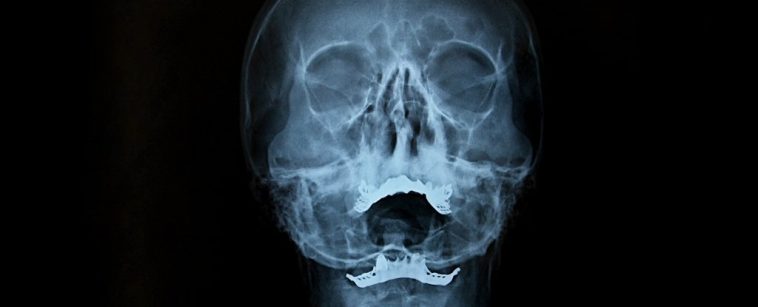

Channel in the human skull. (Herisson et al., Nature Neuroscience, 2022)

While the findings have not yet been replicated among humans, it’s likely that our brains show a similar system that bypasses the blood-brain barrier. Using micro CT scans, the authors have already found similar tiny channels connecting the human skull to the brain’s meninges, each about 1.5 millimeters in diameter.